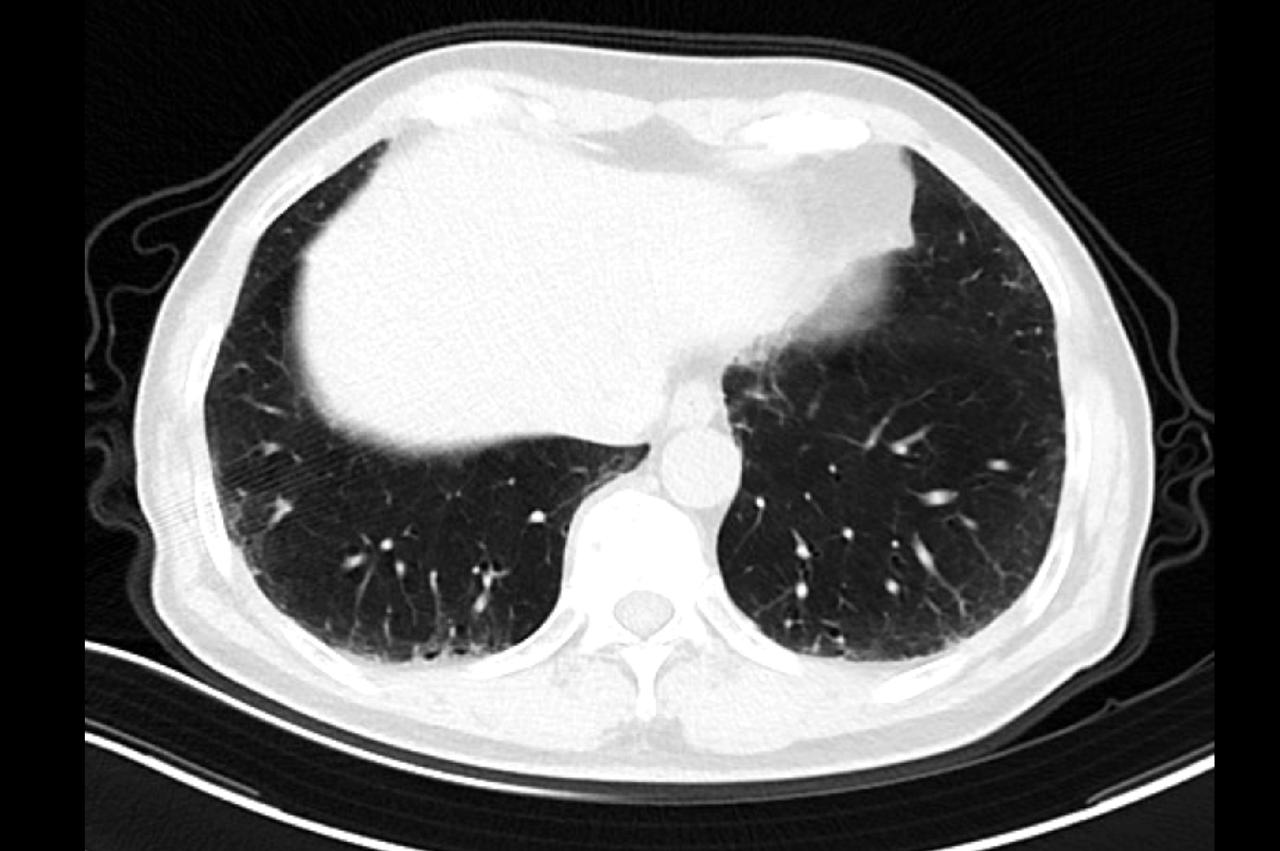

体检发现肺结节,不用慌!大部分结节都是“乖宝宝”,但少数“坏分子”(恶性结节)会